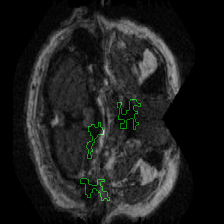

Figure 1 presents attribution maps generated using PWIG for a selection of MRI scans across all four diagnostic categories. The highlighted regions (in green) correspond to the areas that contributed most significantly to the model’s decision. Notably, we observe consistent emphasis on anatomical structures that align with clinical markers of dementia, including cortical and subcortical regions. For instance, in the moderate and mild dementia examples, the model focuses on regions exhibiting visible atrophy or abnormal morphology. In contrast, attribution maps for non-demented subjects appear more diffuse and less concentrated, reflecting the model’s detection of normal anatomical patterns.

The results in Figure 1 demonstrate that PWIG can effectively produce interpretable and clinically meaningful explanations for model predictions in medical imaging tasks.

Figure 1: PWIG attribution maps across dementia categories using the OASIS-1 dataset. Green overlays indicate regions with the highest attribution scores.